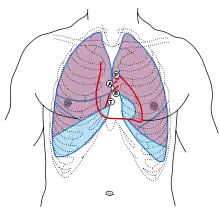

The closing of the mitral valve and the tricuspid valve constitutes the first heart sound (S1), which can be heard with a stethoscope. It is not the valve closure itself which produces the sound but the sudden cessation of blood flow, when the mitral and tricuspid valves close.. Abnormalities associated with the mitral valve can often be heard when listening with a stethoscope.